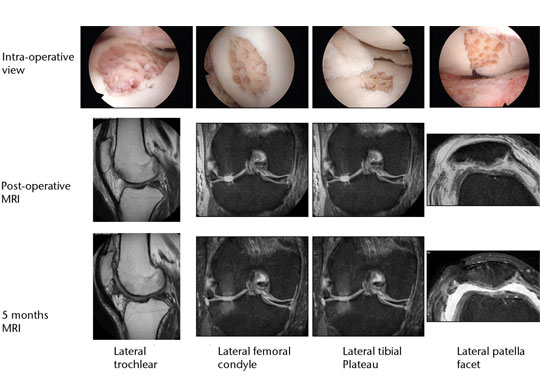

A similar approach can be used in combined chondral injuries and meniscal tears. Figure 2 shows the arthroscopic fi ndings of a 61-year-old orthopaedic surgeon and recreational skier. Two years following injury and after an unsuccessful arthroscopic debridement he was troubled by a persistent knee effusion, limited walking distance and lateral patellar maltracking with chondral lesions over the lateral patellofemoral joint. There was also an associated degenerated lateral meniscus and chondral injury in the lateral compartment. The patient underwent arthroscopic subchondral drilling together with lateral patellar release and subsequently received stem cell therapy. MRI scans at five months showed evidence of repair and regeneration accompanied with clinical improvement.

Fig. 2 Intra-operative views following subchondral drilling with the corresponding MRI scans after surgery and progressive healing at five months of the lateral trochlear, lateral femoral condyle, lateral tibial plateau and lateral patellar facet.